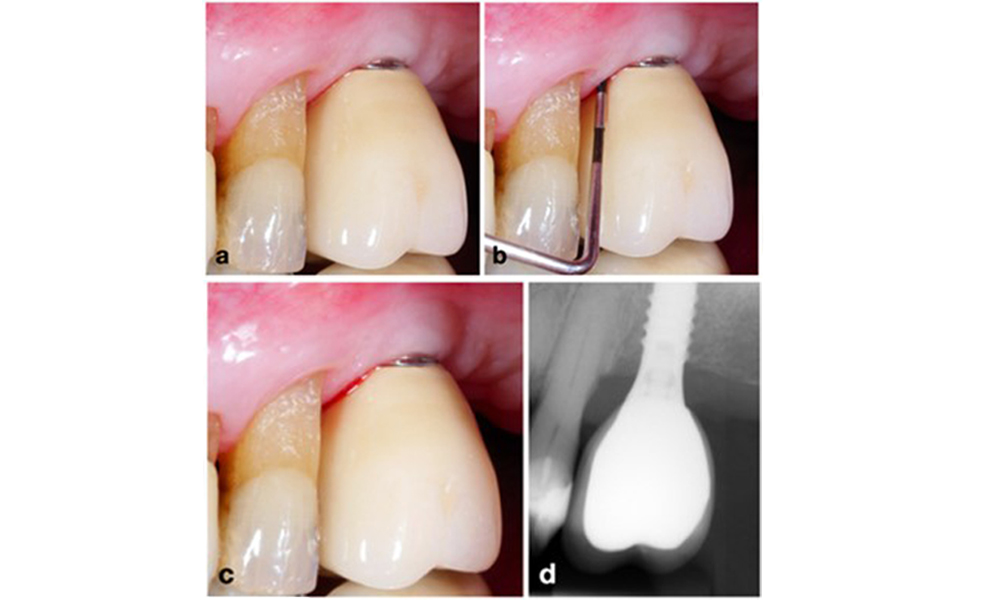

Restaurationen des gesamten Zahnbogens mit unterschiedlichem Grad der Periimplantitis bei einigen der Implantate. Das Implantat an Position 21 ist mit Sondierungstiefen von bis zu 9 mm (a), Sondierungsblutung, Eiterbildung am periimplantären Sulkus und einer vestibulären Fistel (b-c) stark betroffen. Die Röntgenaufnahme zeigt einen Knochenverlust von etwa 50 % für das Implantat mit Periimplantitis an Position 21, während das Implantat an Position 23 nur einen begrenzten Knochenverlust aufweist, entsprechend etwa dem, was bei Implantaten dieses Typs nach der Ersteinheilung zu erwarten ist (d).

Abb. 2. Restaurationen des gesamten Zahnbogens mit unterschiedlichem Grad der Periimplantitis bei einigen der Implantate. Das Implantat an Position 21 ist mit Sondierungstiefen von bis zu 9 mm (a), Sondierungsblutung, Eiterbildung am periimplantären Sulkus und einer vestibulären Fistel (b-c) stark betroffen. Die Röntgenaufnahme zeigt einen Knochenverlust von etwa 50 % für das Implantat mit Periimplantitis an Position 21, während das Implantat an Position 23 nur einen begrenzten Knochenverlust aufweist, entsprechend etwa dem, was bei Implantaten dieses Typs nach der Ersteinheilung zu erwarten ist (d).